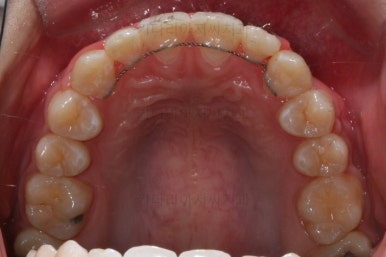

이번에 사용한 장치는 메탈장치였고, 치료 초기에는 매복치를 제대로 꺼내는데 초점을 맞췄어요.

처음 장치를 부착한 이 후 8개월이 흐른 시점이네요. 꽤나 오랫동안 천천히 송곳니를 가지런하게 해줘요.

치료 10개월째의 모습입니다.

이정도면 다 끝난 것 같은 느낌이 드시지 않나요? 과개교합도 개선시켰고 매복치아 덧니도 가지런하게 했어요.

왜소치 좌우로 틈을 일부러 만든 상태입니다.

그 후에 임시 개념으로 사이즈를 크게 만들어 줬어요.

사이즈를 크게 한 뒤에도 약간의 틈이 남아서 다시 틈을 줄여주는 과정을 진행했어요.